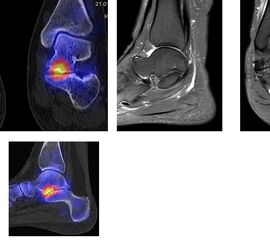

Die Abbildungen 4.2.a bis d zeigen den typischen Aspekt einer talacalcanearen Coalitio. Es besteht nur eine linksseitige, symptomatische Coalitio talocalcaneare (4.2.a und c); das 35 Tage zuvor angefertigte MRT zeigt keine auffälligen Signalveränderungen (4.2.b und d).

Abbildung 4.3. zeigt die Ursache für rechtsseitige Sprunggelenksbeschwerden bei einem Patienten mit talocalcanearen Coalitionen: nur die osteochondrale Läsion an der distalen rechten Tibia ist die Ursache des Schmerzes. Die bilateralen talocalcanearen Coalitionen sind asymptomatisch.